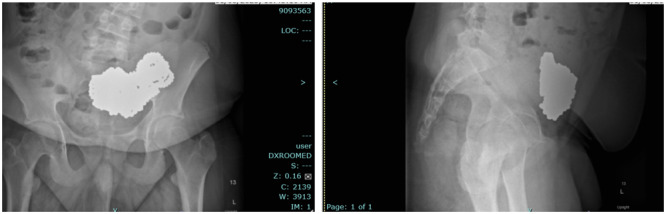

Multiple magnet ingestion warrants appropriate and timely management to avoid serious complications. We report a case of a 14-year-old male with multiple magnet ingestion. Serial abdominal X-rays with misinterpreted foreign body location delayed appropriate management.